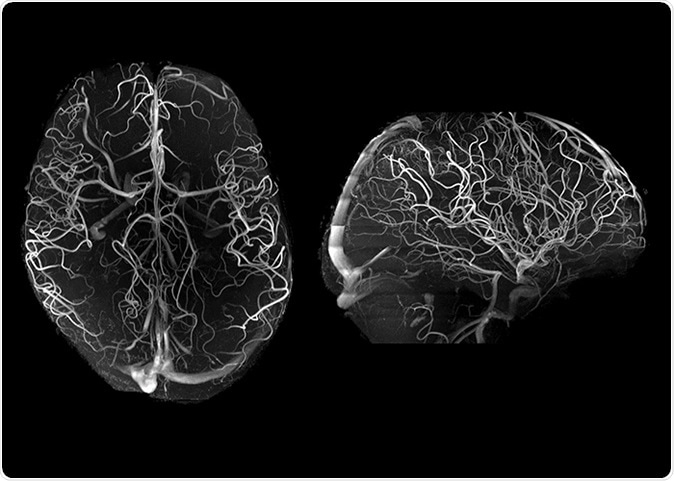

7T angiography in late life depression patients with the “Tic-Tac-Toe” RF coil system and without the use of invasive contrast agents. While not feasible at 3T, 7T super high-resolution acquisitions (voxel size is 0.2 mm in all directions) significantly improve the conspicuity of small arterioles.

At the same time, small vessel disease in the brain is seen as white matter hyperintensities (WMH) in the brain, and this is linked to depression in older people. However, the exact nature of this change is difficult to trace due to the lack of detail with conventional MRI at 3T, hindering the exploration of the mechanisms underlying depression.

This imaging tool is one of only about 60 in the whole world and has been used to study human anatomy as well as to conduct experiments. At 7T MRI, arterioles in the brain become conspicuous, enabling the study of small vessel disease.